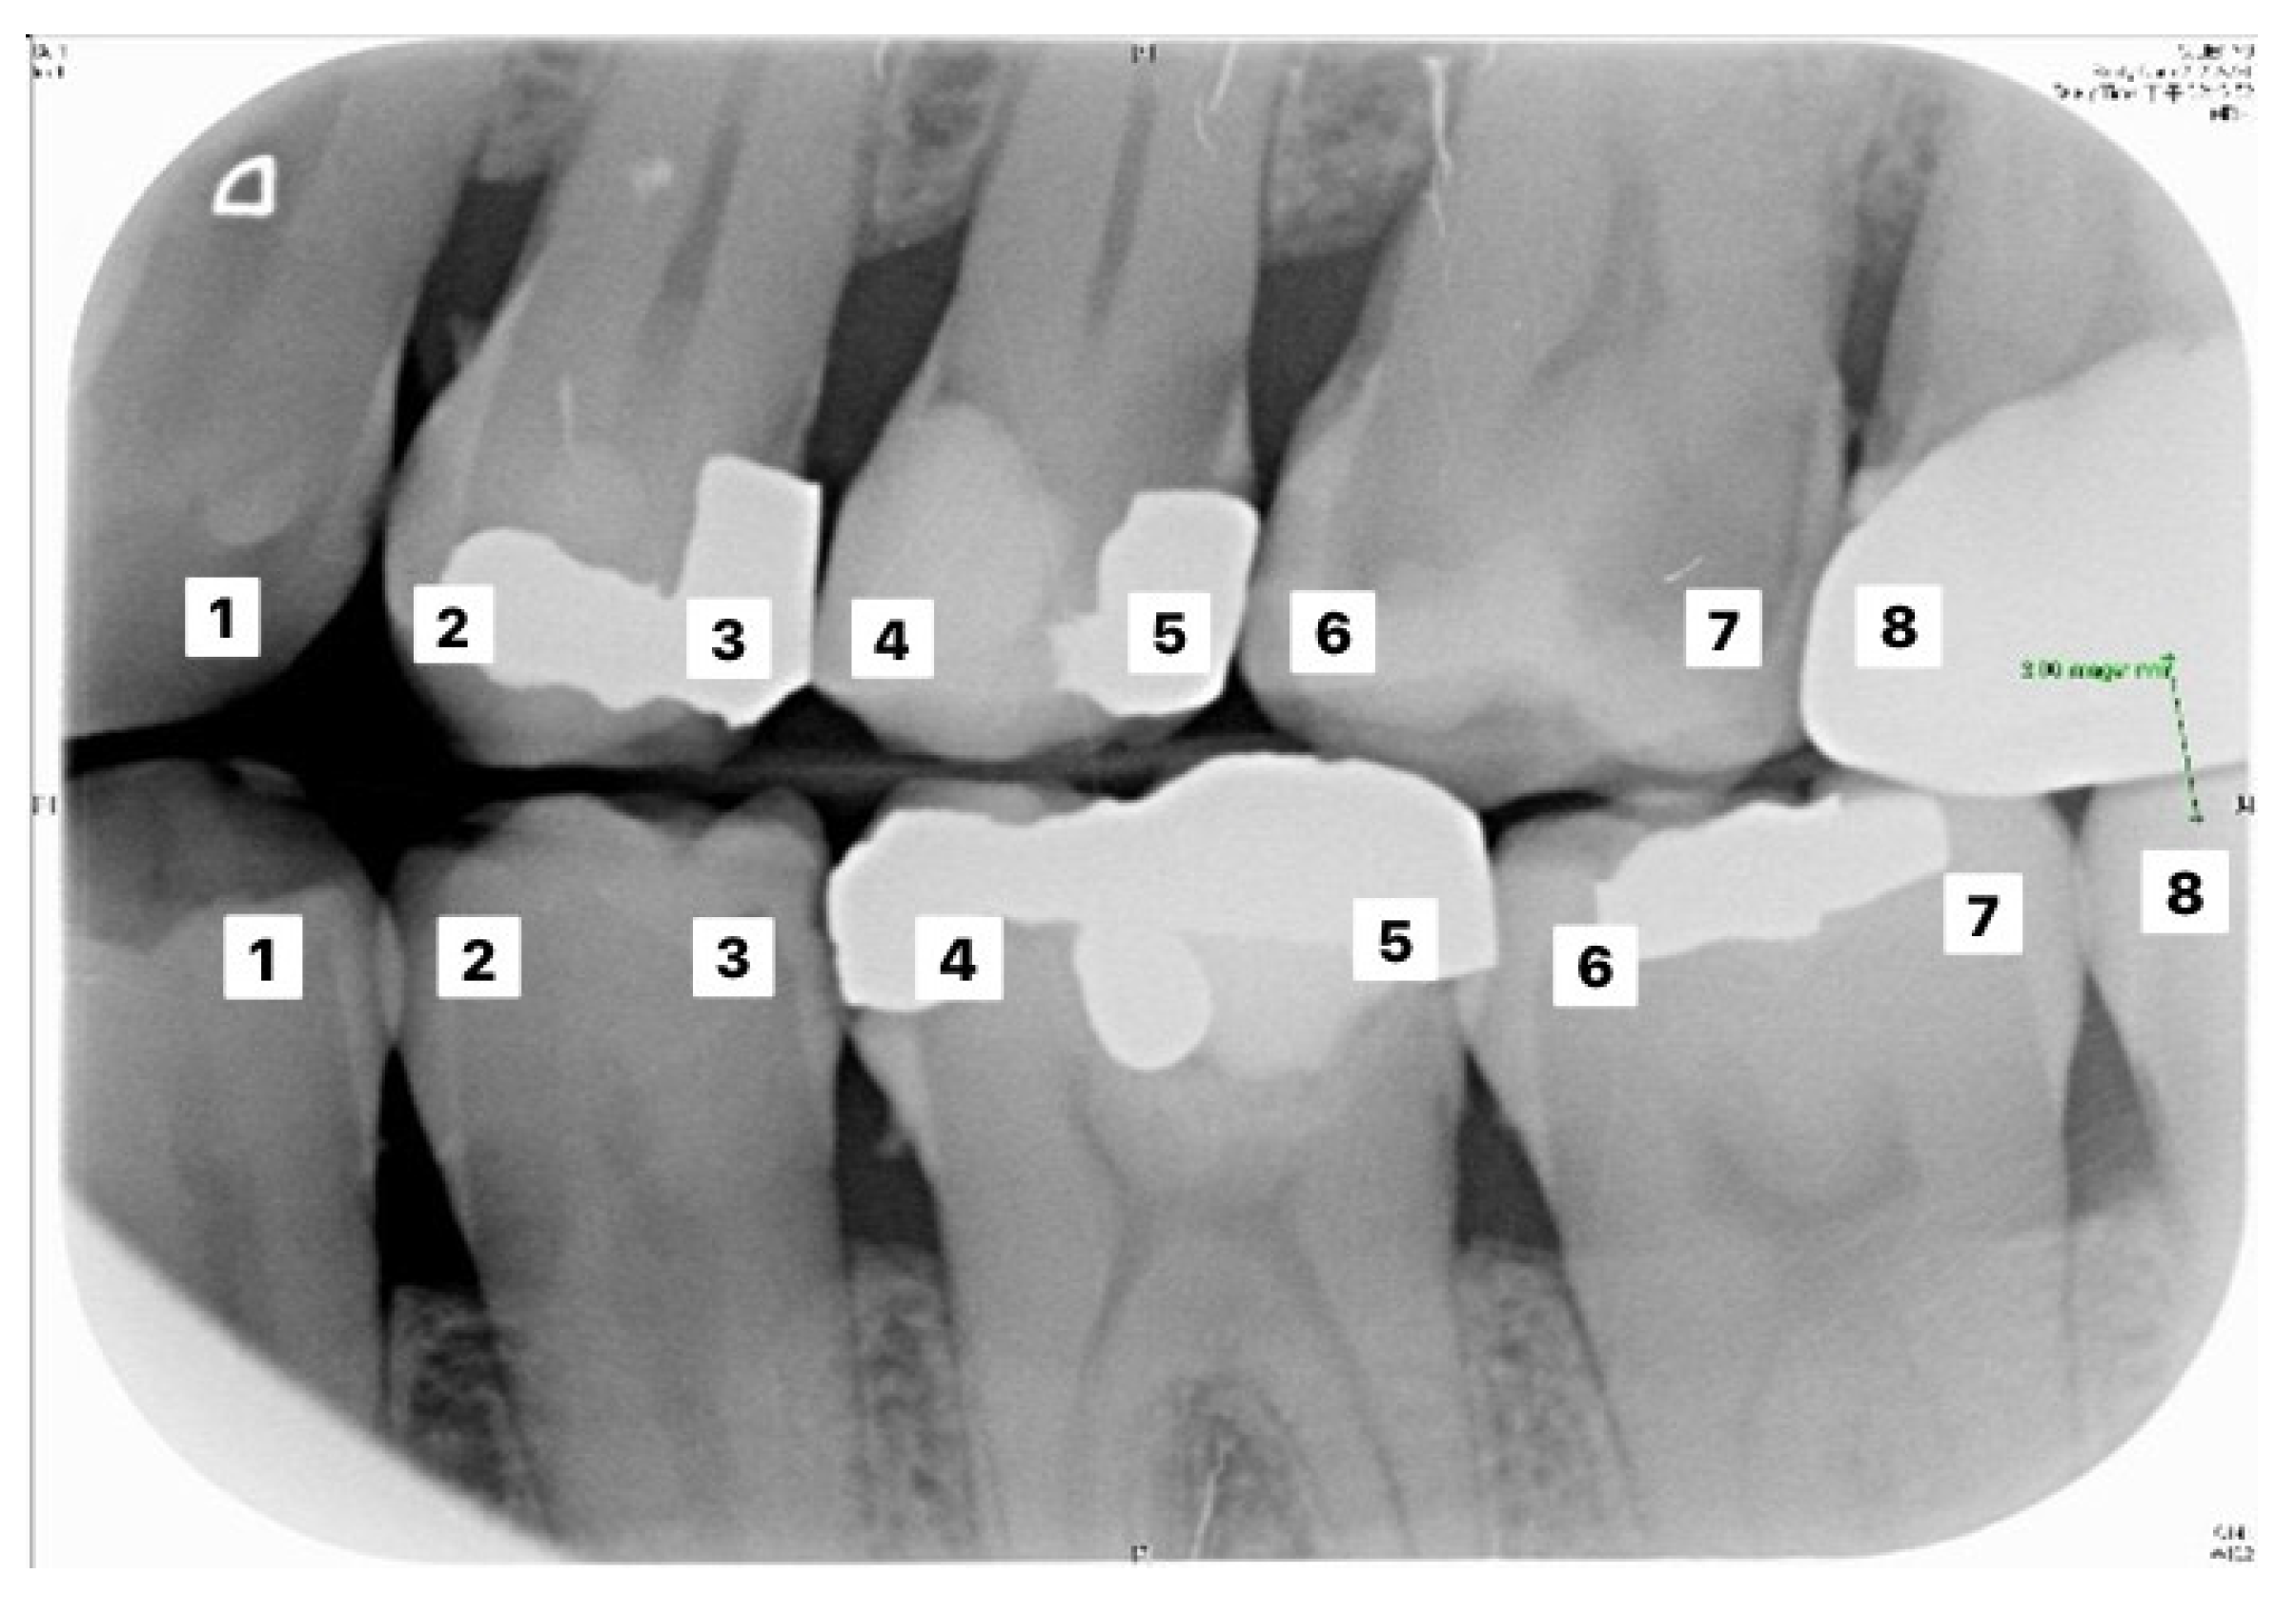

Table 6 and Table 7 correspond to the judgment of the upper and lower rows of teeth in Figure 10. Results show that the accuracy of the proposed model for judging the restorations was 95.56%, which is an improvement compared to Lin et al. [30], with an accuracy of 90.23%. The proposed method in Lin et al. [30] first enhanced the classification features of the image, and then added the regular term and impulse, before establishing a CNN model with the ReLU function. With regard to judging caries, the proposed model in this study showed an accuracy of 90.30%, which was also an improvement compared to Singh and Sehgal [31], with an accuracy of 80.00%, which used a neural network classifier to classify caries. Table 8 and Table 9 are the truth tables of different CNN models.

Table 6.

Upper tooth judgement for teeth image in Figure 10.

Table 7.

Lower tooth judgement for the image in Figure 10.

Figure 10.

Image example of outer teeth for validation (from left to right, in order of 1–8).